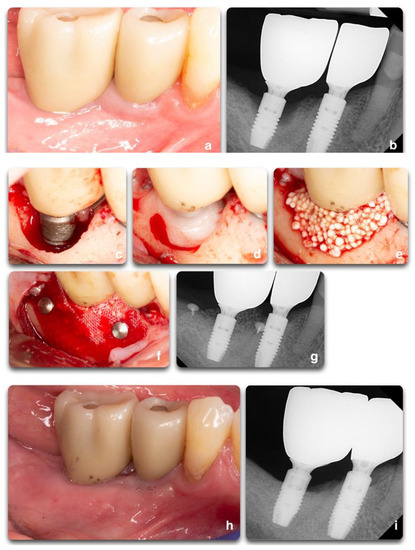

Figure 1.

Representation of peri-implant clinical parameters that, associated, can lead to a diagnosis of peri-implantitis. In the sequence above, BOP/Suppuration (a), radiographic bone level ≥ 3 mm (b) in combination with PD ≥ 6 mm (c).